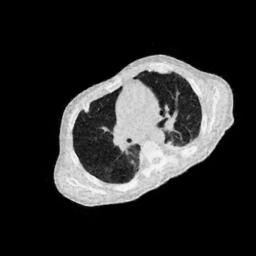

4.3 Few-View CT Reconstruction

In this section, the reconstruction performance of our proposed framework under few-view conditions will be tested. For the parallel-beam and fan-beam geometry, the number of views increases from to , uniformly distributing from to and to respectively. Such settings provide a complete benchmark of reconstruction performance, ranging from extremely sparse to relatively complete, full-view CT reconstruction. The experiment results are shown in Fig.5. Additionally, the ground truth, few-view ( views), and full-view ( views) CT reconstruction results of different methods are shown in the first and third rows of Fig.7 (parallel-beam, LIDC-IDRI dataset), and Fig.8 (fan-beam, LIDC-IDRI dataset).

(a) Ground Truth

43.87dB

(b) ASD-POCS

47.96dB

(c) RBP-DIP

34.46dB

(d) DIP

26.63dB

(e) MED50

29.03dB

(f) RED-CNN